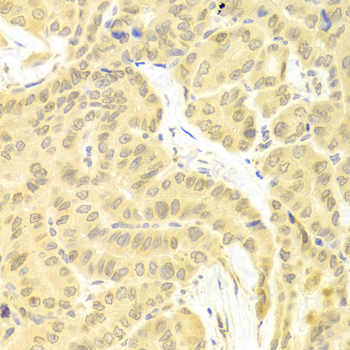

Immunohistochemistry of paraffin-embedded human thyroid cancer using CFLAR antibody. |